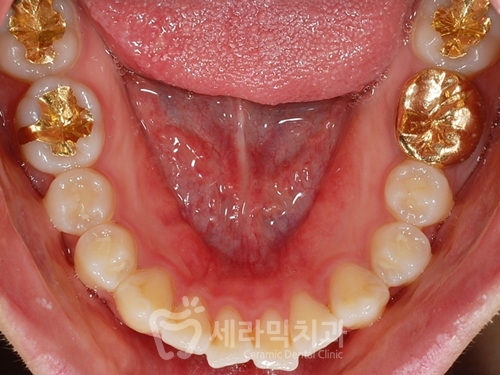

(1) 문제점 진단

치아돌출 뿐 아니라,

잇몸돌출이 동반되어 있는 걸 확인할 수 있으며

얼굴 옆 라인을 보면

돌출입과 함께, 턱선이 밋밋한

'무턱' 경향을 보여줍니다.

치아의 배치 자체는 고른 편이나,

치아가 전체적으로 바깥 쪽으로 뻗쳐있습니다.

(2) 치료계획

치아돌출과 잇몸돌출이 동반된 돌출입이라

치아 4개 발치를 통해 돌출입을 개선합니다.

옥니가 되지 않도록

상악에는 하이토크 브라켓을 사용합니다.

미니스크류(mini-screw)를 이용하여

돌출을 최대한 개선합니다.